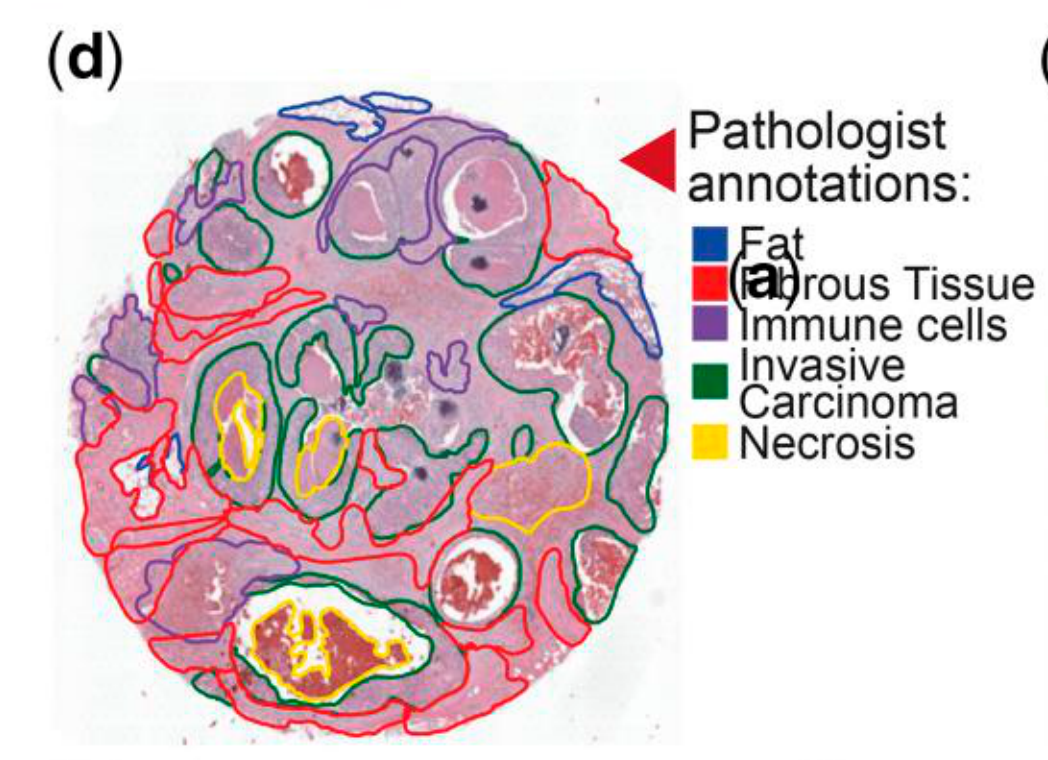

Jiang X. et al. - 2024

How are pathologist-defined tissue regions distributed across a cancer tissue section?

Biological

Tissue

Abstraction

Partial

Chart Type

Histological image

Communicative/Contextualization

Highlighting

Comparative Design

None

Layout

Spatial : Physical

Scalability Strategy

None (Item-level)